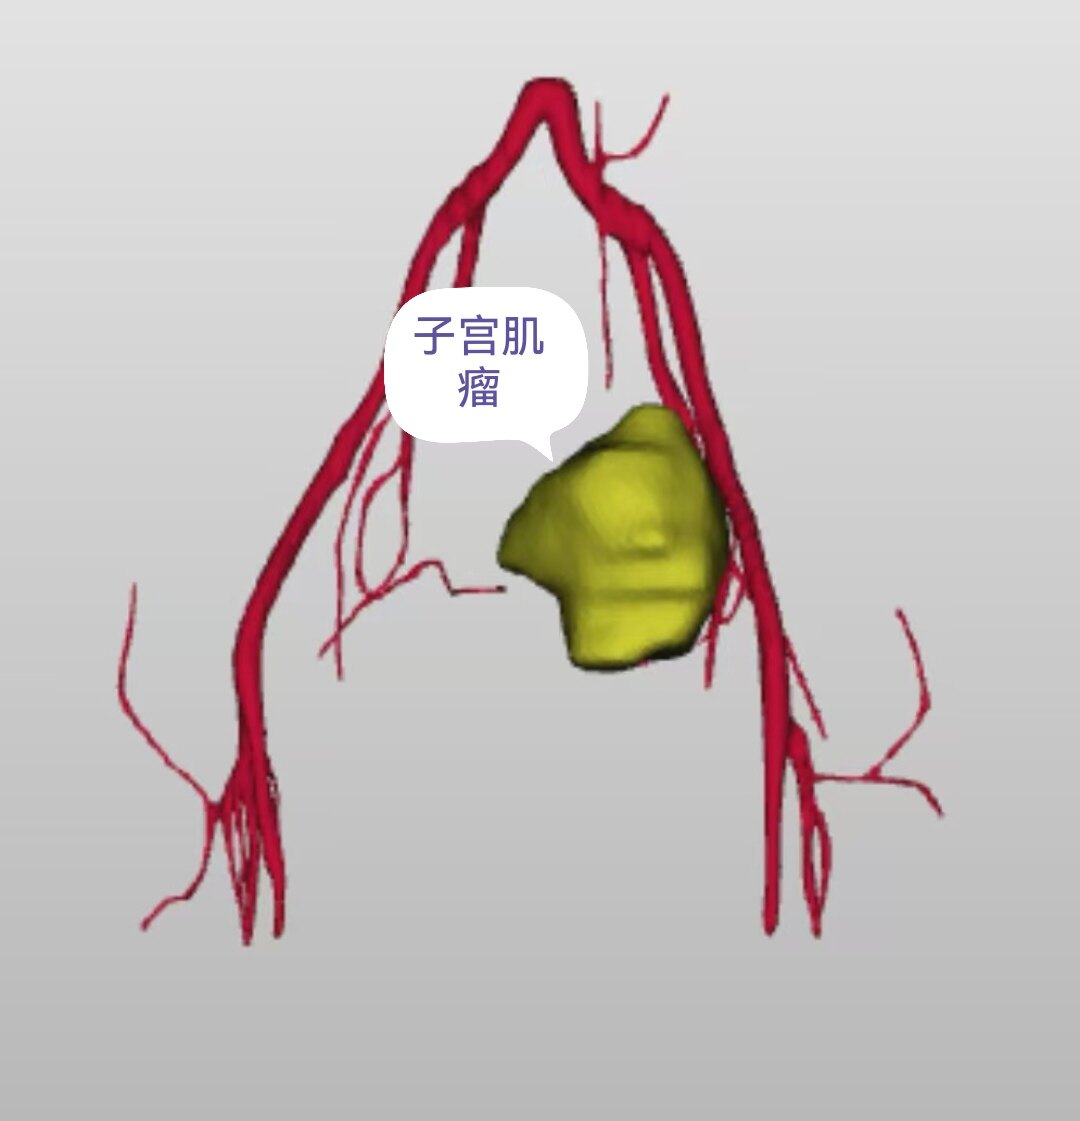

子宫肌瘤是育龄女性最常见的良性肿瘤,约30%女性深受月经量大、贫血、腹痛等困扰(图1)。传统手术需切除子宫或剥除肌瘤,让许多女性望而却步。如今,一种仅需“打针”的微创技术——子宫动脉栓塞术(UAE),已经成为保宫治疗的新希望。

图1 CTA图像显示子宫肌瘤的供血动脉为子宫动脉